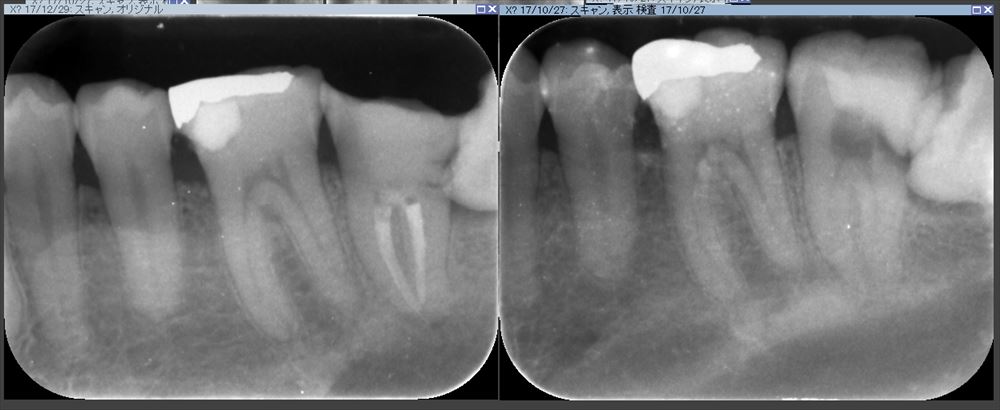

術前は感染だらけ

症状もなくレントゲンでも問題ありませんでした。

術前(右)根管充填後(左)